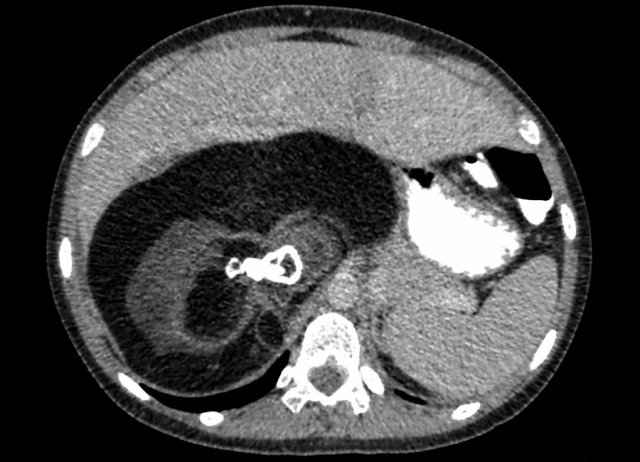

A two-year-old boy presented with a swelling in the abdomen.

On ultrasound a large solid tumor was seen in the upper abdomen. Some calcifications are present. The mass probably originates from the liver. It slides over the right kidney.

Continue with the MRI.